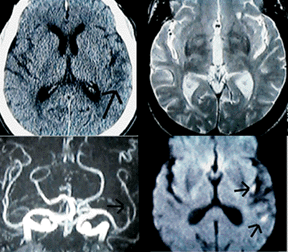

See how much more quickly the image on the right loads. This is the 16 k JPEG image showing CT and MR diffusion images of an acute stroke. Do you notice any appreciable difference in image quality? The GIF image on the left takes up nearly 66 kilobytes, taking 23 seconds to download at 28.8 kbs versus 5 seconds for the JPEG.